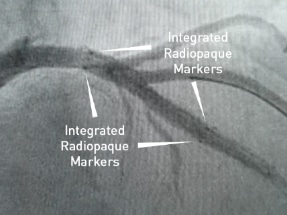

EluNIR-PERL is Medinol’s most recent advancement in coronary stent technology. This seventh-generation stent features a unique stent design which utilizes a distinctive CoCr framework composed of struts with varying widths and integrates radiopaque markers into its structure.

Furthermore, the stent features a specialized radiopaque enhanced metal spring tip designed for navigating through complex anatomies. These design elements are intended to equip physicians with precise positional information, facilitating accurate stent placement during PCI procedures.

Reinforced radiopaque tip and stent markers for accurate delivery and stent positioning

Medinol’s patented Flexx² technology is based on a tapered spring tip designed to eliminate tip flare out and buckling while enabling simultaneous flexibility and pushability. Now with enhanced radiopacity to facilitate positioning and navigability.

Enhanced Metal Spring Tip

Enhanced Tip Radiopacity

Tip Visibility

First implantation of the EluNIR-PERL elastomeric Drug Eluting Stent, the only DES with two radiopaque markers at each end of the stent.